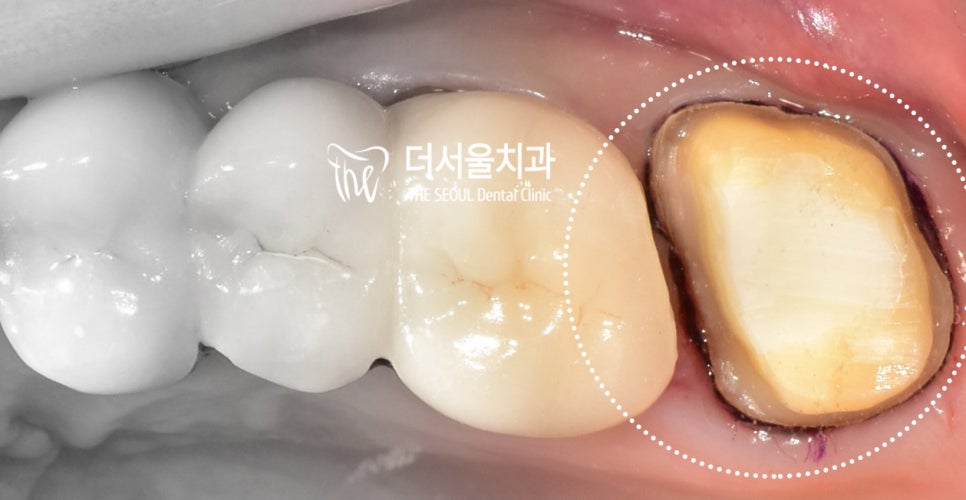

자 신경치료라 부르는,

과정을 다 마친 뒤에는 코어(core)라는

과정을 거치게 됩니다.

(기둥을 만드는 것 )

그 다음에는 이제 기둥과

크라운이 연결 될 수 있도록

외형을 다듬게 되죠.

(잇몸이 까맣게 보여지는 것은,

code 라는 것을 심은 겁니다.

인상채득이라 해서 ‘본 뜨기’ 를 할 때

조금 더 정밀하게 할 수 있도록

하는 과정입니다.)

이후, 2주 뒤에 지르코니아 크라운이

만들어져서 수복이 되었습니다.